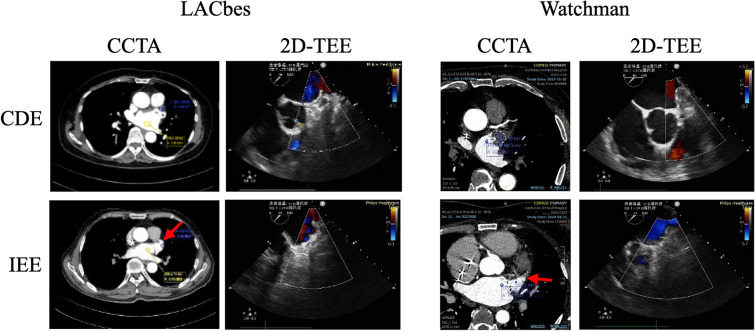

Methods: This retrospective observational study included 168 patients with nonvalvular atrial fibrillation (AF) who underwent successful LAAC at Shanghai Ninth People's Hospital between January 2022 and December 2023. IDE was assessed using transesophageal echocardiography (TEE) and cardiac computed tomography angiography (CCTA) at 6 months post-procedure. IR was evaluated using the triglyceride-glucose (TyG) index, triglyceride-to-high-density lipoprotein cholesterol (TG/HDL-c) ratio, and metabolic score for insulin resistance (METs-IR). Logistic regression analysis was performed to identify independent predictors of IDE, and a predictive model was constructed.

Results: Among the 168 patients included in the analysis, 43 (25.5%) exhibited IDE, as determined by TEE or CCTA at 6 months post-procedure. Patients with IDE had a significantly higher body mass index, triglyceride (TG) levels, total TG/high-density lipoprotein ratio, TyG index, METs-IR index, and D-dimer levels, as well as a larger maximum LAA orifice diameter (p < 0.05). Multivariate logistic regression identified D-dimer, METs-IR, and maximum LAA orifice diameter as independent predictors of IDE. The predictive probability model incorporating these factors demonstrated high discriminatory ability (area under the curve 0.800, 95% confidence interval 0.71-0.89, p < 0.0001). The optimal predicted probability cut-off value was 0.284, achieving a sensitivity of 76.2% and a specificity of 85.2%.